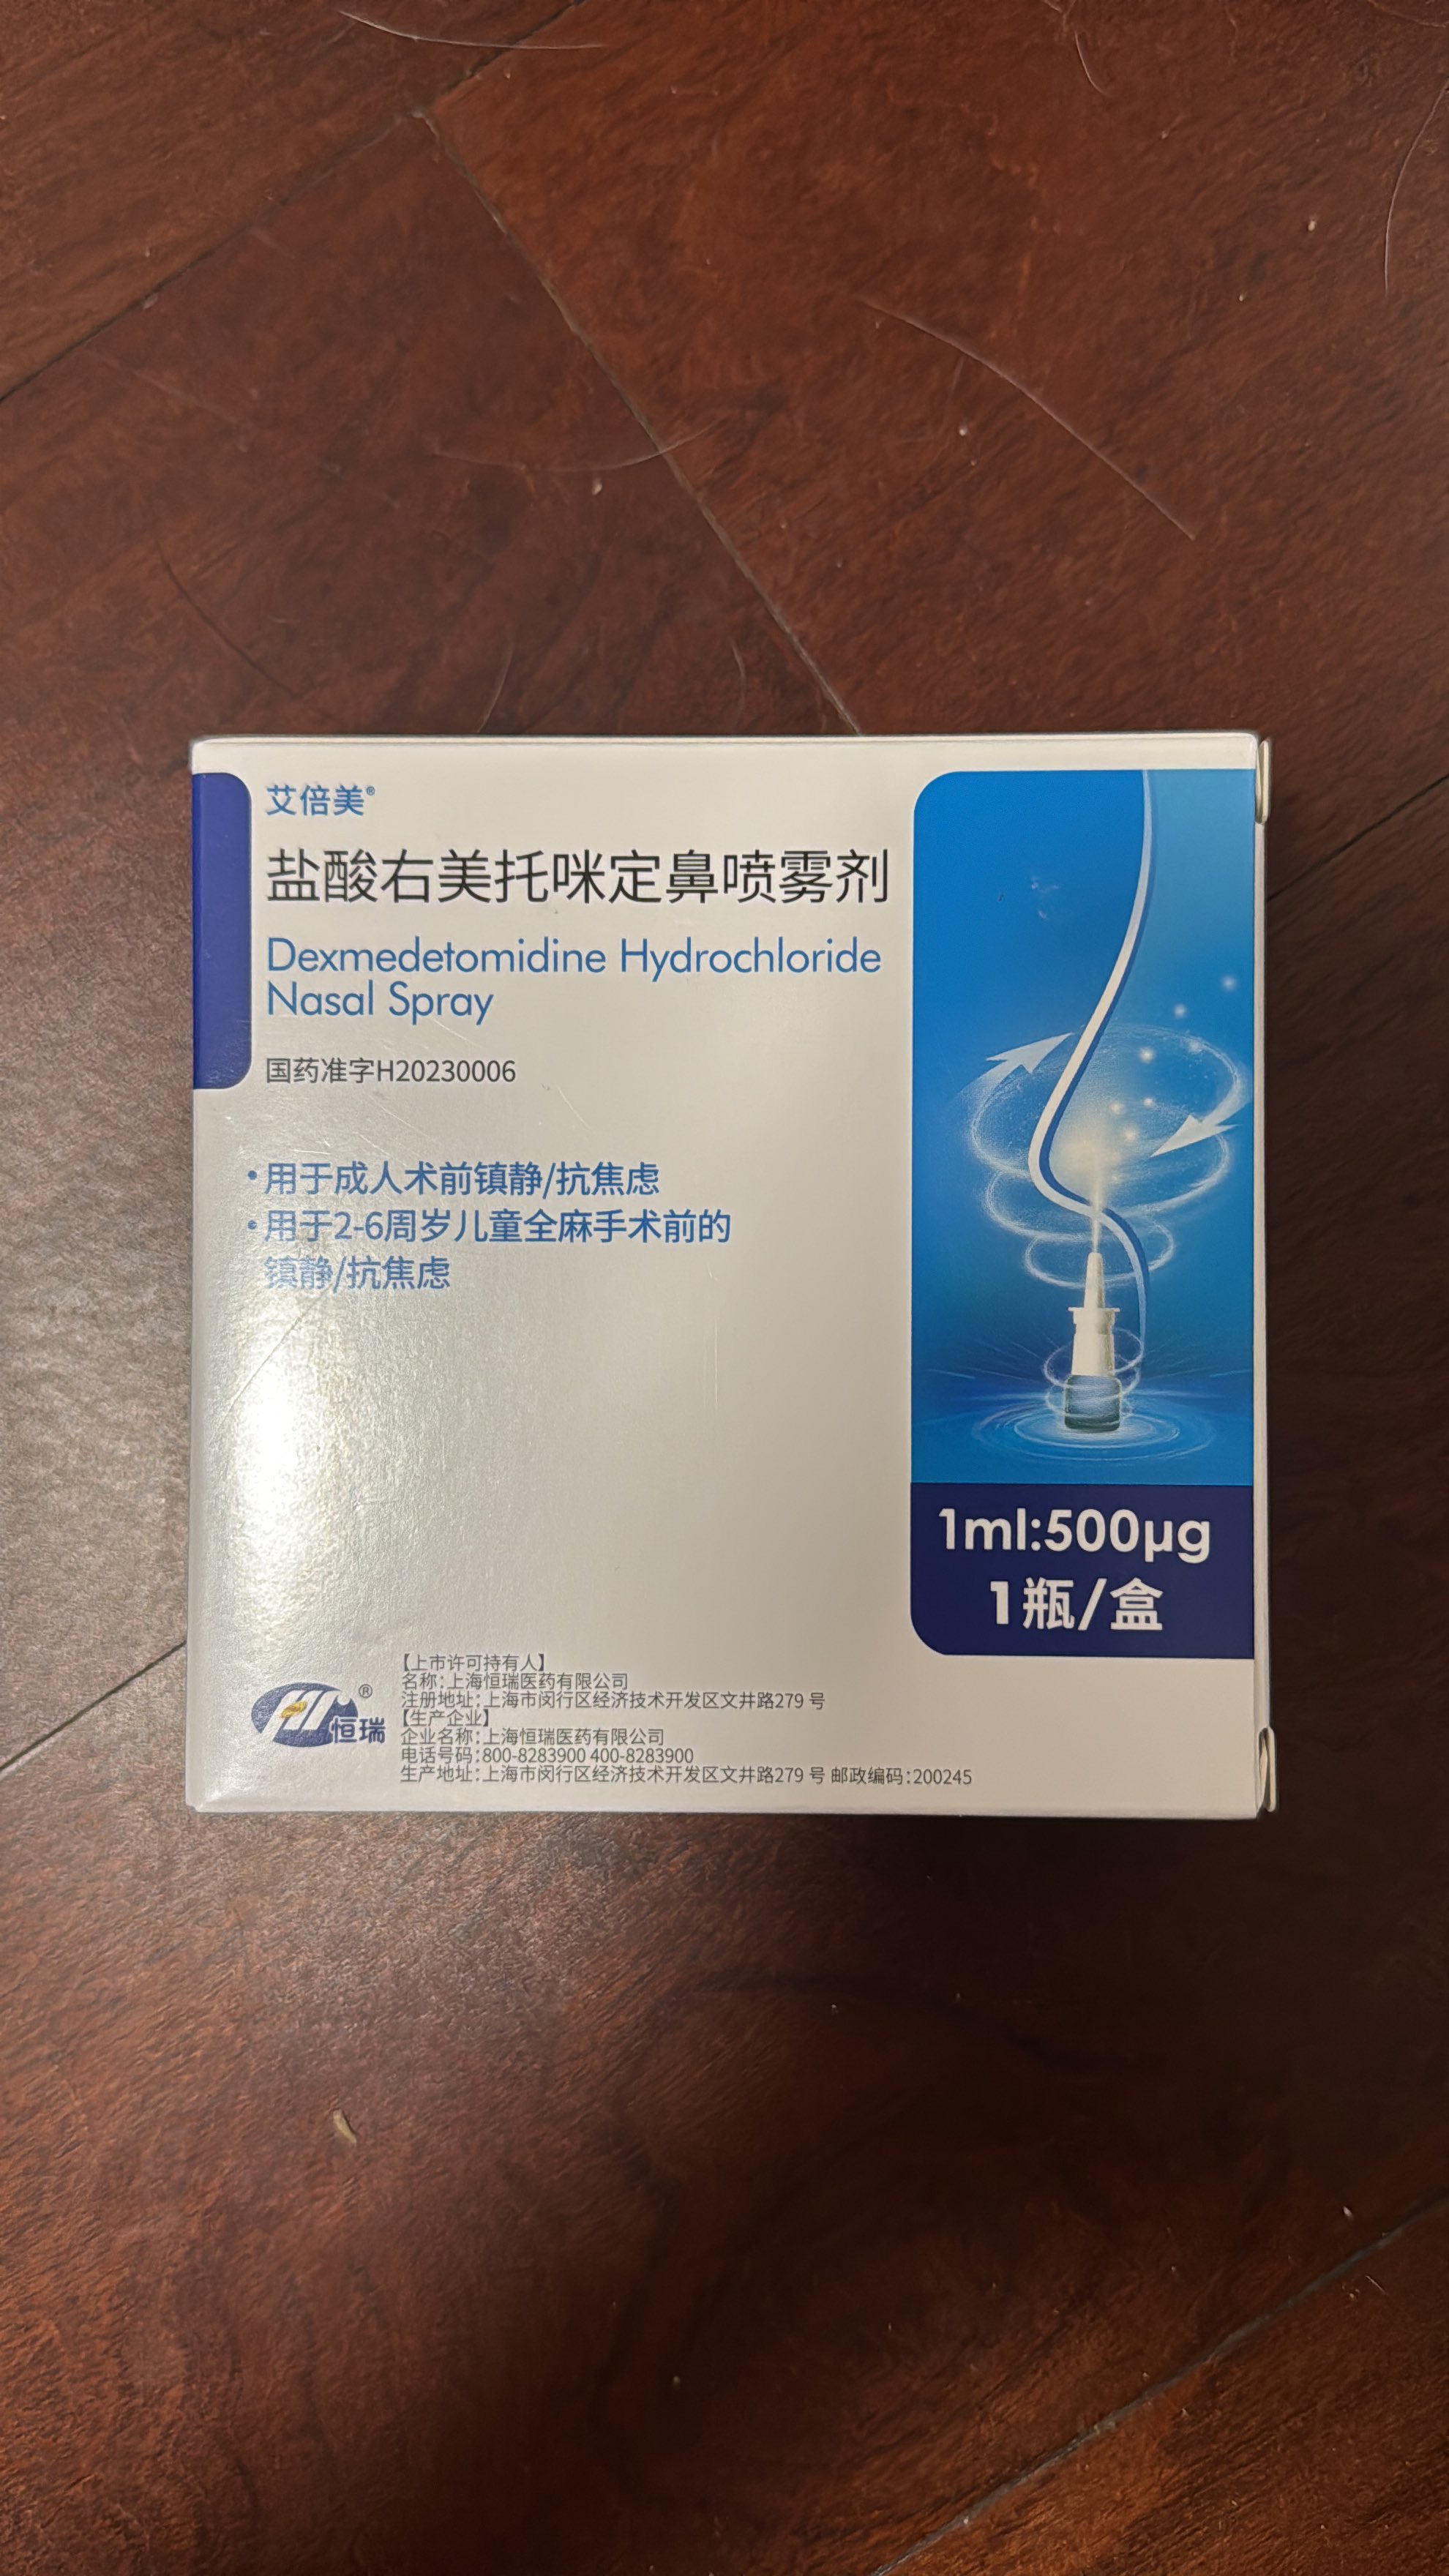

吃完唑吡坦会干一些难绷的事情,昨天睡不着疑似气急败坏了抽了0.5ml右美托咪定就是iv,还奇奇怪怪挑了个很痛的头静脉

后面不记得了,醒了灯开着的还以为是做梦,对着针孔一脸不可置信地整理记忆

你别说还扎得挺好的()按压时间估计也够,一点淤青也没有,不知道哪来的意志力 https://t.co/KxtfAUVSmb